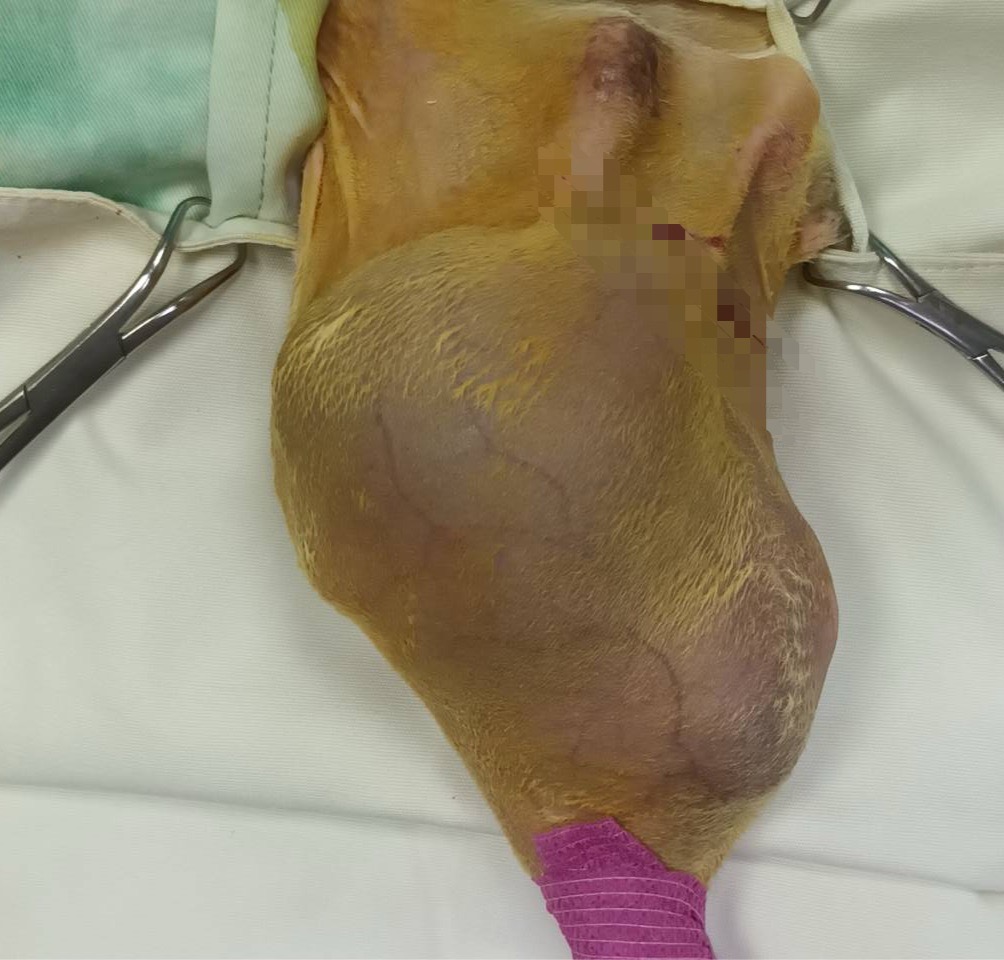

九歲大的小咪,就是不幸罹患『骨肉瘤』的案例!大約三個月前,主人發現小咪的後腿腫起,初期只當作是外傷撞擊引起的腫脹,並不太在意;不料左後腿(大腿骨)越腫越大,變得無法正常走路,這才帶到台南『啄木鳥動物醫院』看診,啄木鳥立刻用X光檢查,再做病理採樣分析,確診是可怕的『骨肉瘤』無誤,由於『骨肉瘤』轉移肝臟、肺臟、全身的機率很高,只好毅然決定截肢。

所以,看到腿部腫起,就要趕快做X光檢查,以免延誤治療時機。若不幸罹患『骨肉瘤』更要考慮手術(整支腿)切除,若幸運切除乾淨,就不容易再轉移到別的地方,同時手術完,還要視嚴重程度,持續以化療、放療治療;如果切除乾淨,平均還有四年的餘命。但若遇到難以切除乾淨的部份,例如:軸骨頭、脊椎等部位,很難切除乾淨,平均餘命便只剩8~12個月,實在不容小覷。

『骨肉瘤』術後照顧安排無障礙環境,術後追蹤,每3~6個月回診。

『骨肉瘤』的術後照顧需要特別用心!由於截肢造成行動不便,建議把貓砂盆、及食物區放低,類似人類『無障礙』設施,讓貓咪容易進出,並減少耗體力的活動需求。至於術後追蹤,必須定期檢查肺臟、肝臟,有無轉移的現象。建議術後第一年,每三個月做胸腔X光、及腹腔超音波檢查;即使一年以後,也需要每六個月檢查一次,才能杜絕『骨肉瘤』轉移的潛在危機。